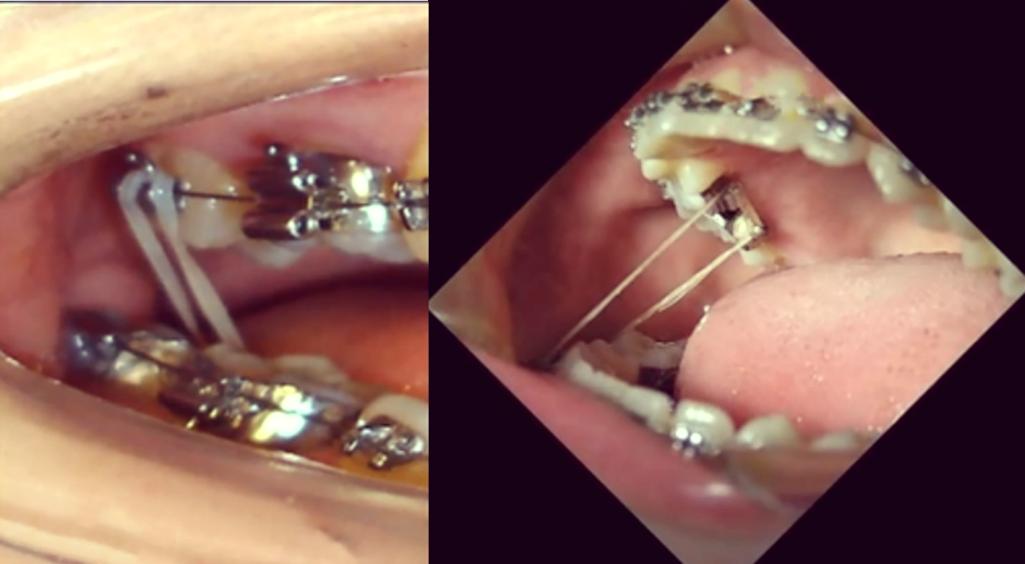

| 弓丝就位 | 将弯制好的弓丝(如镍钛圆丝、不锈钢方丝)按顺序插入托槽槽沟,确保末端回弯到位,避免刺伤黏膜。 | 弓丝插入器、持针器 | 弓丝需与托槽槽沟紧密贴合,若存在间隙,可能导致牙齿移动失控。 |

| 结扎固定 | ①不锈钢丝结扎:用结扎钳将0.008-0.010英寸不锈钢丝“8”字形缠绕托槽翼与弓丝,末端剪断后弯向牙面;②弹性圈结扎:选用合适直径的弹性圈(如灰色、蓝色)套住托槽翼与弓丝,确保无扭转。 | 结扎钳、不锈钢结扎丝、弹性结扎圈 | 不锈钢丝结扎需力度均匀,避免单侧过紧;弹性圈需定期更换(2-4周),因弹性会随时间衰减。 |

| 末端处理 | 检查结扎丝末端是否光滑,用打磨车或持针器将尖锐部分磨圆,防止口腔黏膜溃疡。 | 剪刀、打磨车 | 患者若主诉黏膜刺痛,需及时复诊检查末端,必要时调整或更换结扎装置。 |